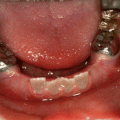

The exact number of developmental defects is not known, but it certainly is in the hundreds with new conditions still being described in the literature. For example, a newly described condition that affects the first permanent molar and sometimes permanent incisors (molar incisor malformation – MIM) has just recently been described for the first time [15, 34]. The first permanent molars have a thin pulp chamber and abnormal root formation, and the etiology and prevalence are unknown at this time (Fig. 1.1). There are many known hereditary and environmental conditions associated with abnormalities in tooth number (both too many and too few). The medical history, in some cases, will readily provide the cause for missing teeth, such as a child received extensive head and neck radiation and/or chemotherapy for cancer while the dentition was in its early developmental stages [8]. In other cases, the etiology will be more elusive as there may be a noncontributory medical history and no family history of missing teeth. As will be discussed in Chaps. 3 and 4, congenitally missing teeth can be associated with a syndromic condition, or it can occur as a nonsyndromic condition.

Fig. 1.1

The molar malformation that is referred to as molar incisor malformation is readily evident in this panoramic radiograph that shows the second primary and first permanent molars and maxillary permanent incisors are all affected